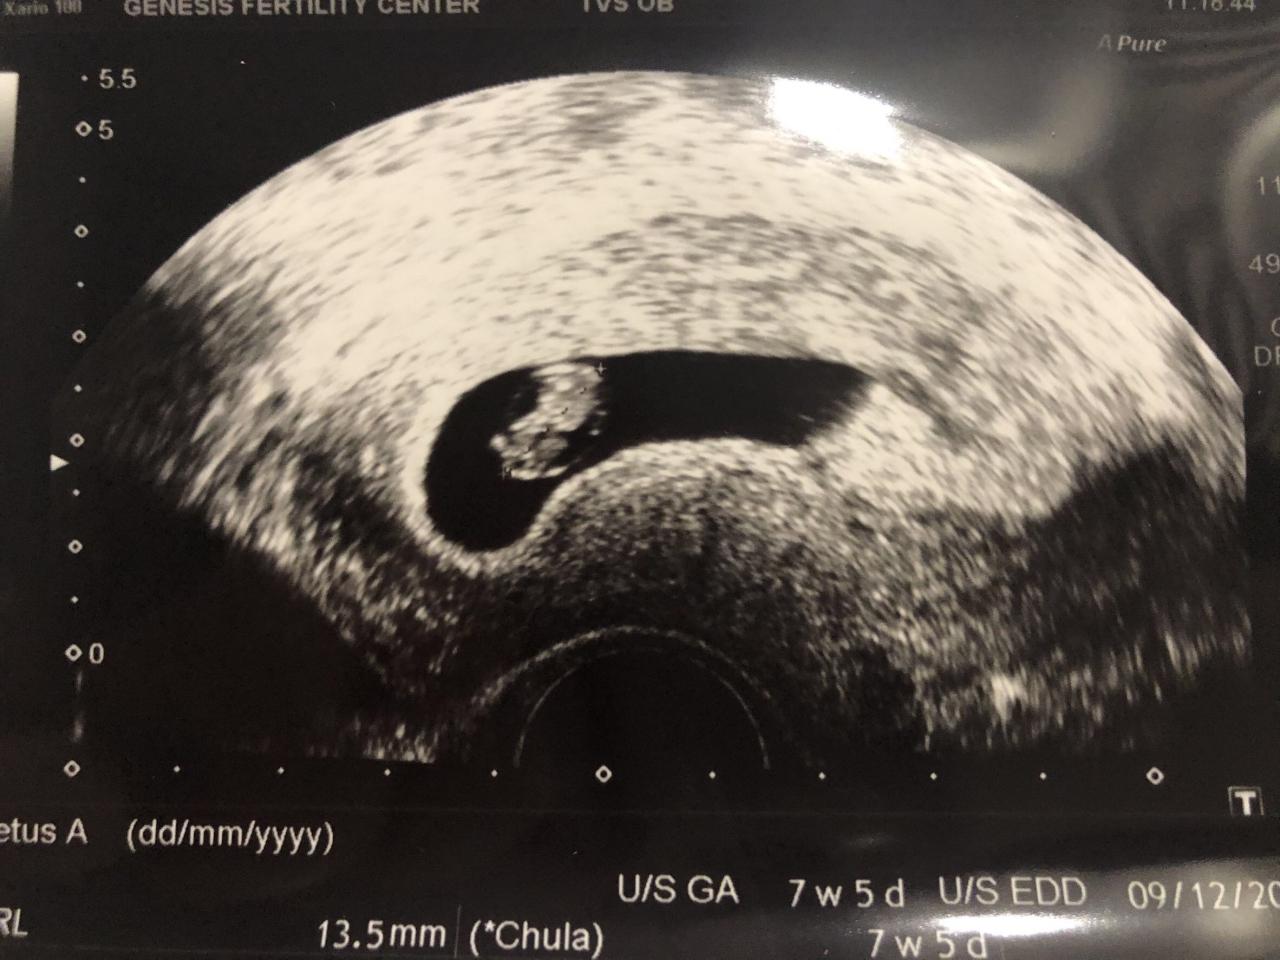

ยิ้มไม่หุบมีความสุขที่สุดหลังจากได้เห็นภาพลูกครั้งแรก สำหรับว่าที่คุณพ่อ ต๊ะ บอยสเก๊าท์ หรือ วินรวีร์ ใหญ่เสมอ ที่ล่าสุดได้ลงคลิป VDO ในอินสตาแกรมของตัวเอง ระหว่างที่พาภรรยาคนสวย บุ๋ม มินตยา ไปอัลตราซาวนด์

เมื่อว่าที่คุณพ่อต๊ะได้เห็นภาพของลูก เจ้าตัวก็เก็บอาการของความสุขไว้ไม่อยู่ยิ้มไปถ่ายคลิปไปตลอดเวลา พร้อมบอกลูกคือสิ่งที่วิเศษที่สุดในชีวิตตัวเองจริงๆ โดยหนุ่มต๊ะ บอยสเก๊าท์ บอกว่า

"มันรู้สึกวิเศษมากๆ ครับ เป็นความรู้สึกที่พิเศษมากอย่างที่ไม่เคยได้จากสิ่งไหนมาก่อน เราอาจจะมีความรู้สึกที่เคยดีใจจากสิ่งต่างๆ มาเยอะ แต่สิ่งที่ดีใจกับการเห็นจากสิ่งที่ได้เห็นลูกมีหัวใจมีสมอง เป็นความดีใจที่วิเศษจากสิ่งอย่างอื่นมากครับ